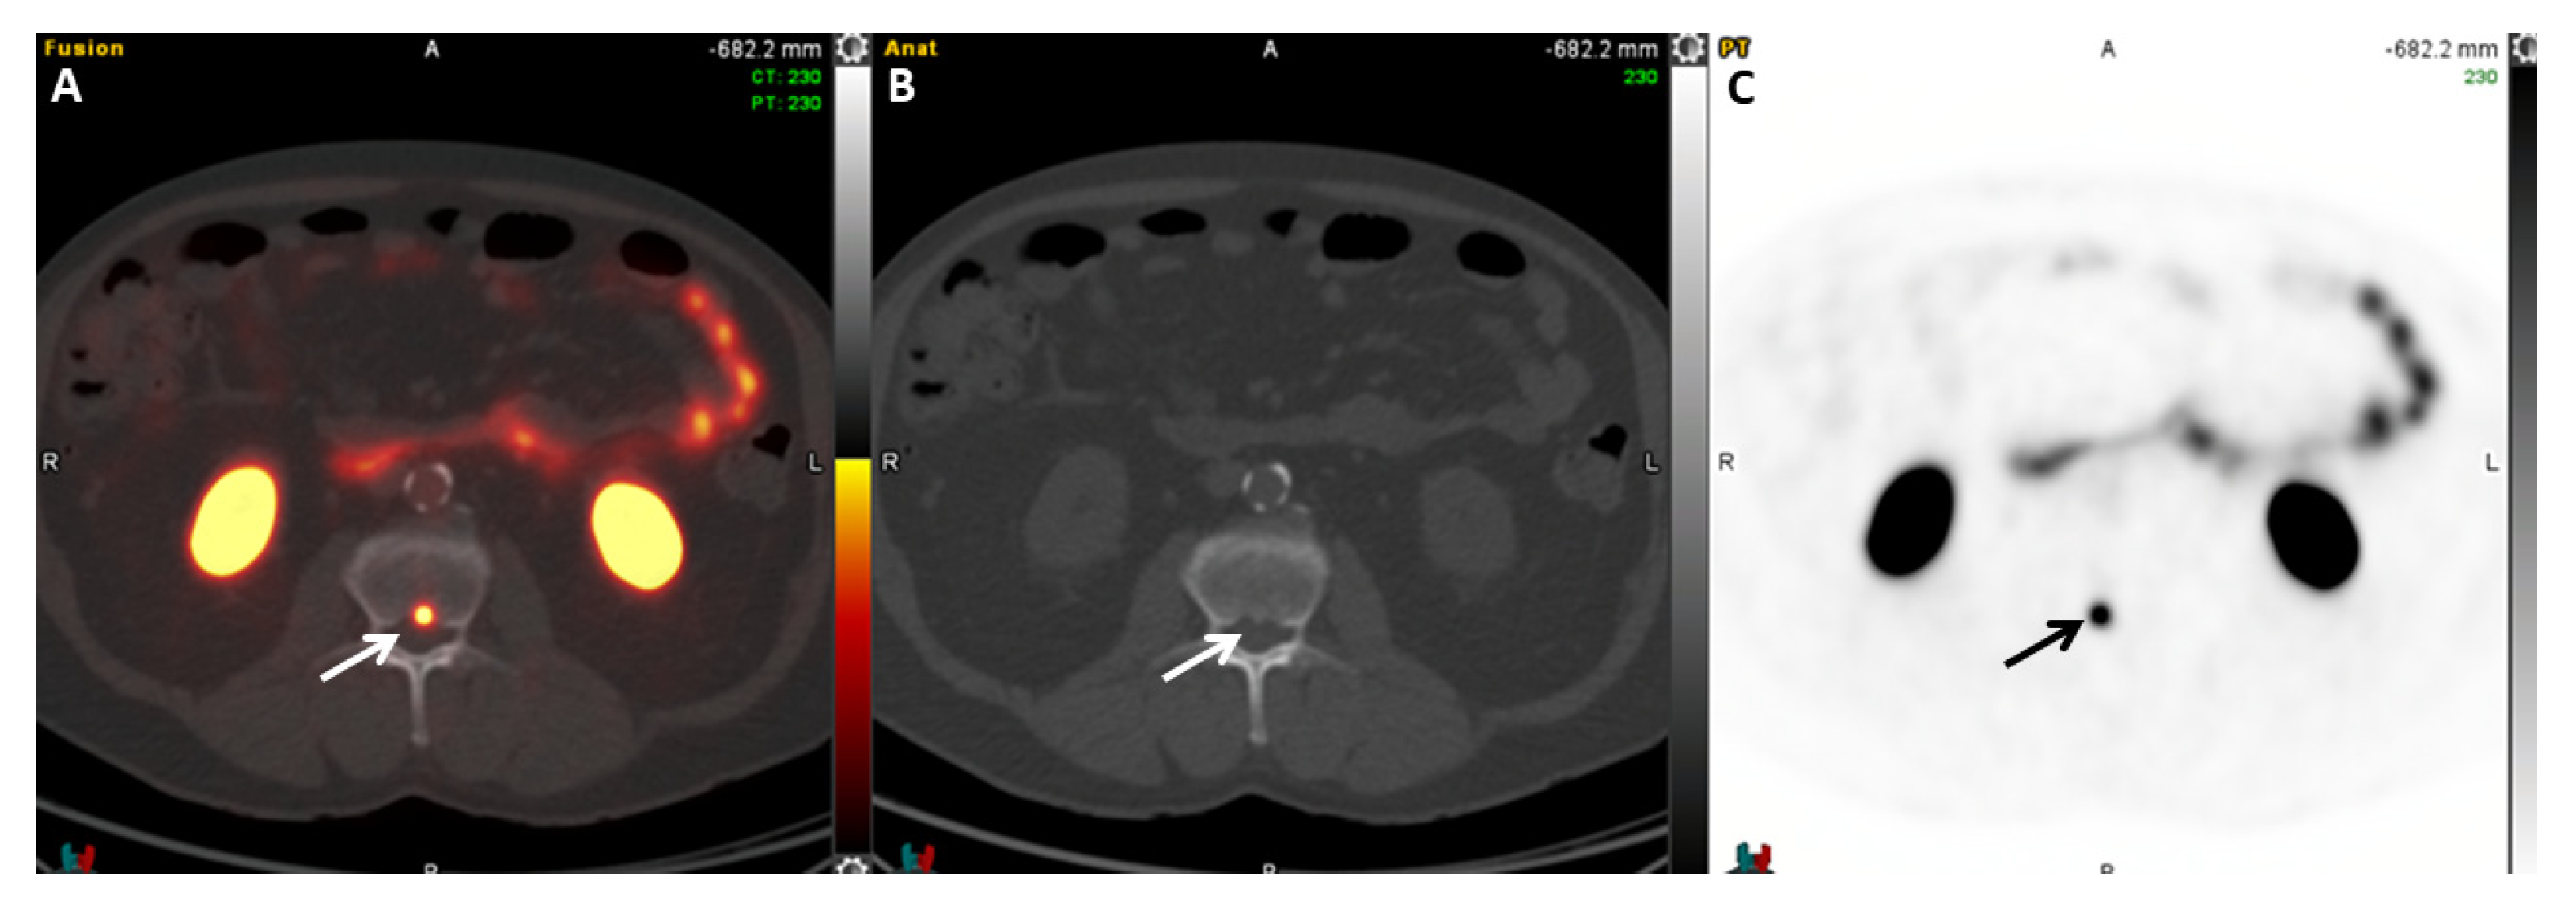

2.5.5. 18F-PSMA-1007

- Pienta, K.J.; Gorin, M.A.; Rowe, S.P.; Carroll, P.R.; Pouliot, F.; Probst, S.; Saperstein, L.; Preston, M.A.; Alva, A.S.; Patnaik, A.; et al. A Phase 2/3 Prospective Multicenter Study of the Diagnostic Accuracy of Prostate Specific Membrane Antigen PET/CT with 18F-DCFPyL in Prostate Cancer Patients (OSPREY). J. Urol. 2021, 206, 52–61. [Google Scholar] [CrossRef]

- Morris, M.J.; Rowe, S.P.; Gorin, M.A.; Saperstein, L.; Pouliot, F.; Josephson, D.; Wong, J.Y.C.; Pantel, A.R.; Cho, S.Y.; Gage, K.L.; et al. Diagnostic Performance of 18F-DCFPyL-PET/CT in Men with Biochemically Recurrent Prostate Cancer: Results from the CONDOR Phase III, Multicenter Study. Clin. Cancer Res. Off. J. Am. Assoc. Cancer Res. 2021, 27, 3674–3682. [Google Scholar] [CrossRef]

- Ulaner, G.A.; Thomsen, B.; Bassett, J.; Torrey, R.; Cox, C.; Lin, K.; Patel, T.; Techasith, T.; Mauguen, A.; Rowe, S.P.; et al. 18F-DCFPyL PET/CT for Initially Diagnosed and Biochemically Recurrent Prostate Cancer: Prospective Trial with Pathologic Confirmation. Radiology 2022, 305, 419–428. [Google Scholar] [CrossRef]

- Rowe, S.P.; Macura, K.J.; Mena, E.; Blackford, A.L.; Nadal, R.; Antonarakis, E.S.; Eisenberger, M.; Carducci, M.; Fan, H.; Dannals, R.F.; et al. PSMA-Based [18F]DCFPyL PET/CT Is Superior to Conventional Imaging for Lesion Detection in Patients with Metastatic Prostate Cancer. Mol. Imaging Biol. 2016, 18, 411–419. [Google Scholar] [CrossRef] [PubMed]